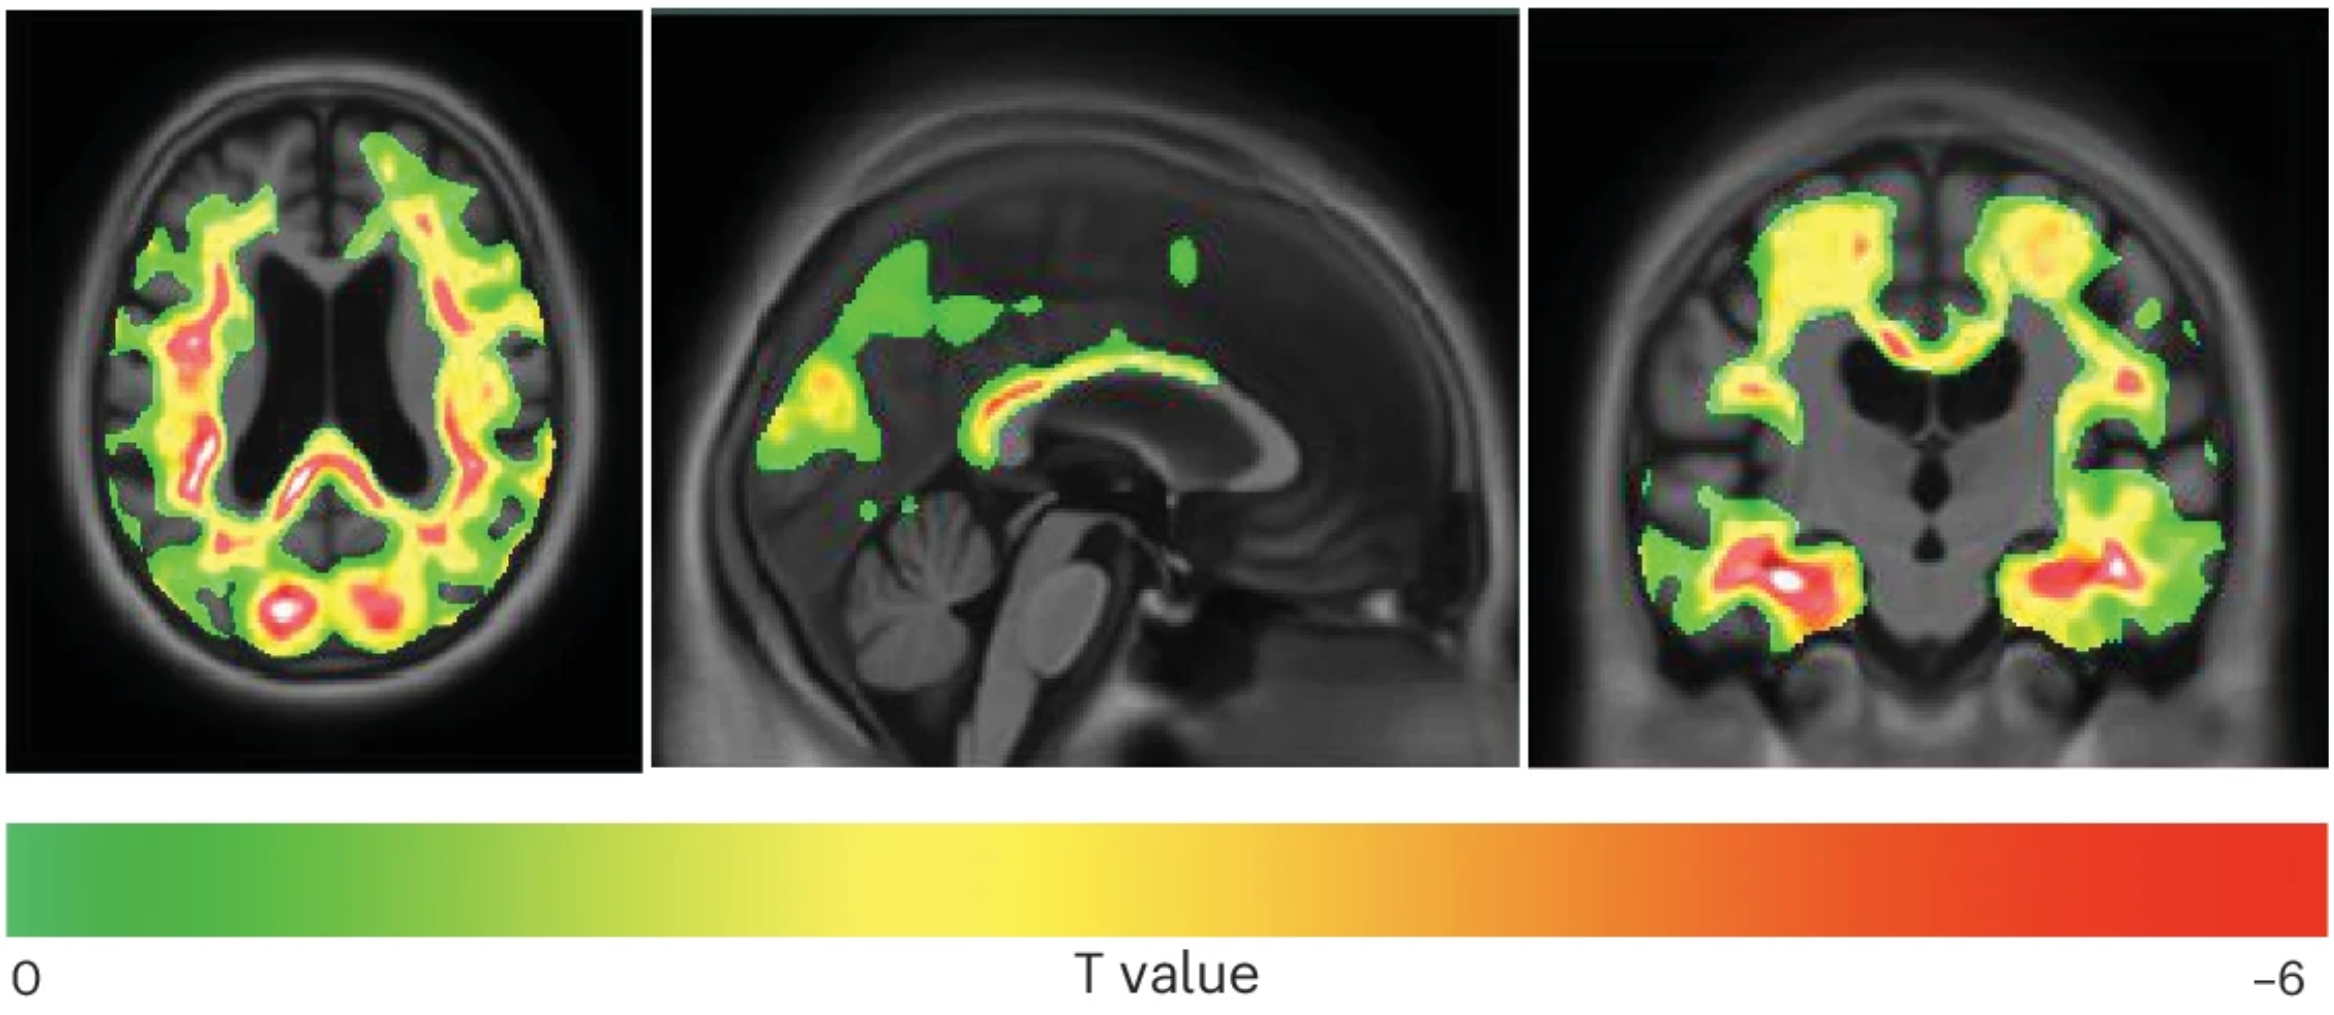

Unlike amyloid-beta plaques, another characteristic of Alzheimer’s, tau pathology is a stronger predictor of disease progression. Traditionally, NFTs have been identified through post-mortem brain staining and, more recently, through tau PET imaging. However, these methods lack sensitivity in detecting early tau changes, which precede the formation of full-fledged tangles.

Detecting these early tau forms could lead to a major shift in Alzheimer’s diagnostics and treatment. Current tau PET imaging can only detect NFTs once a large number have accumulated, meaning patients are often diagnosed too late for effective intervention. In contrast, identifying early tau clumps allows for preemptive treatment, potentially slowing or even preventing cognitive decline.